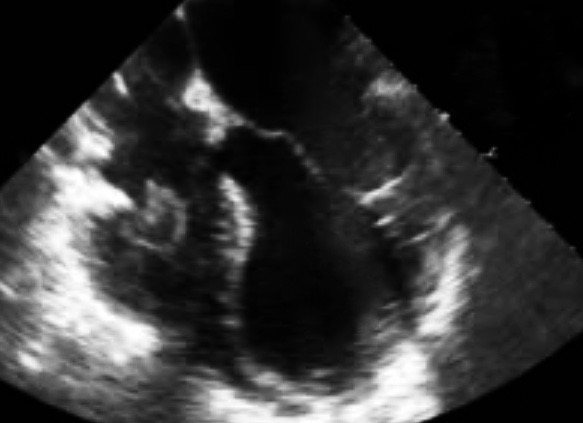

För flera år sedan hade jag en traumapatient som hade fallit från hög höjd och hade ådragit sig flera extremitetsfrakturer, revbensfrakturer och hade GCS 3. Hen hade palpabla pulsar, intuberades på skadeplatsen utan läkemedel. Vid ankomst kunde vi känna femoralispulsar men när NIBP togs var trycket 55/30. eFAST (som utfördes parallellt) visade inget blod i pericardiet, ingen ptx, liten hemothorax vä, inget blod i buken. Slät-rtg bäcken u.a. Kliniskt ingen femur-fx. Efter några minuter var vi på op-salen (vägg-i-vägg med traumarummet på Karolinska) och kirurgen utförde en lateral thorakotomi och klämde av aorta descendens. Blodtrycket steg momentant till >100 varpå det utfördes en laparotomi som bekräftade att det inte fanns blod i buken. I vä thorax fanns ca 100 ml blod. På prov släpptes aorta – trycket föll. Manuella hjärtkompressioner gjordes – trycket steg. Berodde hypotensionen på en neurogen stunning av myokardiet?? Ett TEE visade en väldigt trött vänsterkammare med lite bevarad kontraktilitet basalt. Cirkulationen stabiliserades med adrenalin och noradrenalin-inf och lite senare med milrinon-inf. CT hjärna visade uttalade coup-contrecoup kontusioner.

I den här retrospektiva studien från Seattle gick man igenom echo-fynd hos 139 patienter med isolerad skallskada. Echo hade beställts på klinisk indikation (risk för selection bias). Patienter med känd hjärtsjukdom exkluderades. Av 139 hade 16 LVEF<50% och 21 regional dys/hypokinesi i vänsterkammaren;